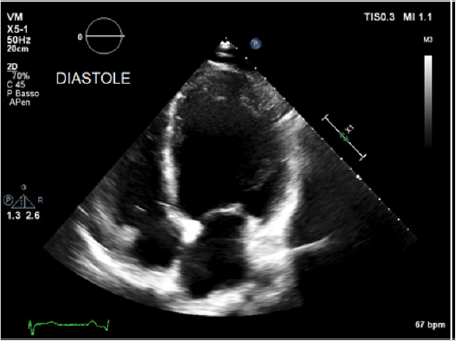

Physical examination showed a muscular man, the apex beat was not evident, the jugular at baseline showed an absent X’ descent with a positive hepato-jugular reflux and heart sounds were regular at the auscultation ; there was also minimal ankle swelling and , bilateral basal crackling rattles were audible at lung auscultation. The ECG showed a sinus rhythm with a frequency of 88 bpm, signs of left atrial enlargement, a left axial deviation and negative T-waves on D1 and aVL and from V4 to V6; no previous recent ECG was available for comparison. Chest X-ray showed pulmonary edema and an acute bronchopneumonia focus. Transthoracic echocardiography (TTE) revealed a dilated cardiomyopathy with severe left ventricular systolic dysfunction (LVEF 23% calculated with the Simpson biplane method) and dilatation (telediastolic diameter 79 mm) with moderate uniform hypertrophy (Figure 1a & 1b). There was grade II diastolic dysfunction (E/A waves ratio 1,9; E wave deceleration time 144 msec), “B-bump” on M-mode examination at the mitral valve level and an average E/e’ at tissue doppler analysis at the upper limit of the “grey zone”: 14 (Figure 2a-2d); global longitudinal peak systolic strain (GLPSS) was -7,4%; the left atrium was dilated; the right ventricle was dilated, slightly hypocontractile (tricuspidal annular plane systolic excursion, TAPSE, 16 mm) with a dilated right atrium; the inferior cava vein showed a normal dimension and collapsibility.

Figure 1a: Transthoracic echocardiography in the acute phase showing significant left ventricular dilatation (EDV 269 ml) and systolic dysfunction (LVEF 23% calculated with the Simpson biplane method): apical 4-chamber views in telediastole.